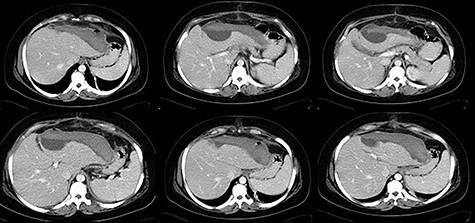

The postoperative period was favorable with lesion regression in serial Computed tomography scan control and was discharged on the 13th postoperative day (Fig. 2).